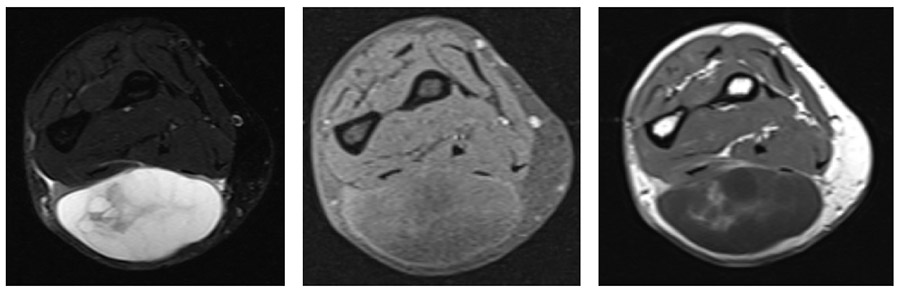

Ameliyat Öncesi: MR’da ön kol dorsal kısımda sınırları düzensiz, heterojen yumuşak doku kitlesi görülmekte.